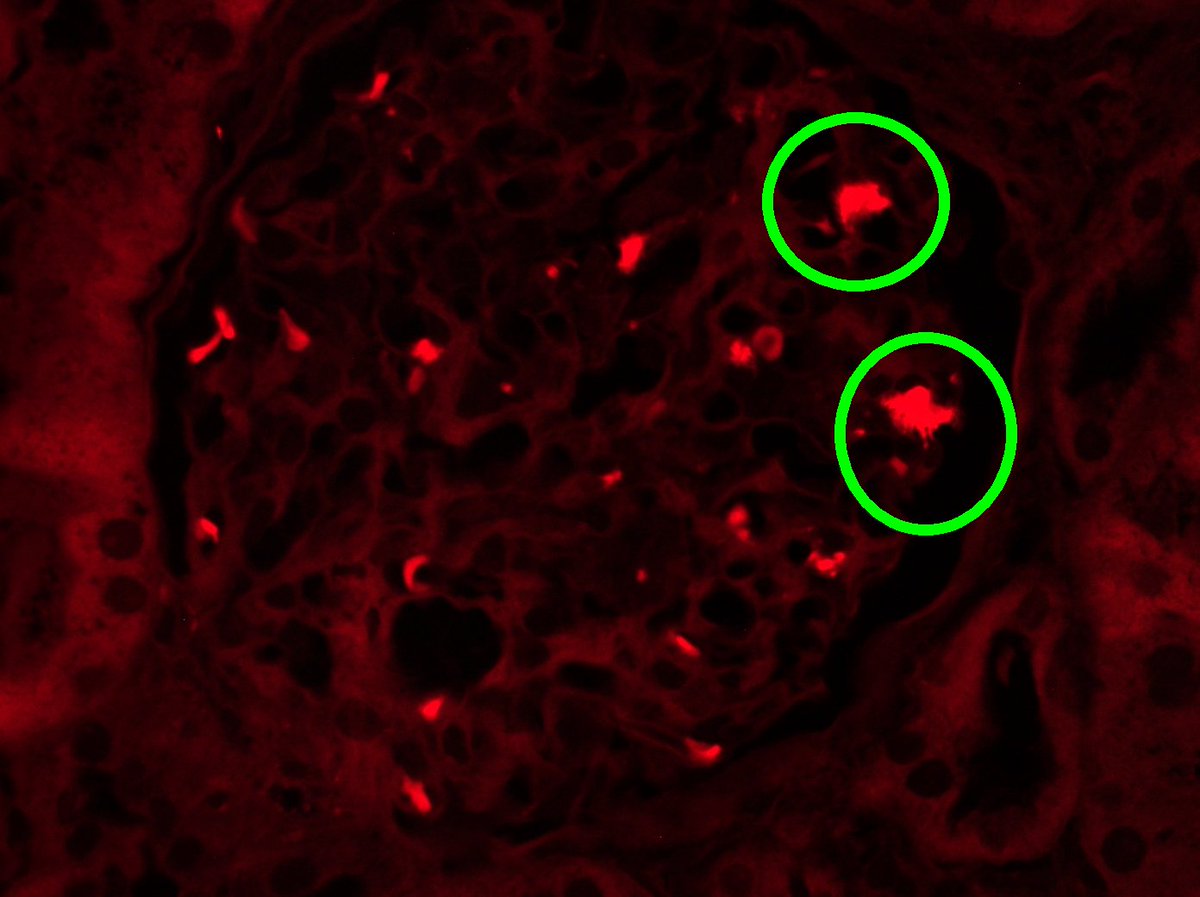

Long weekend often brings urgent cases. Here is one that was STATed, ended up showing anti-GBM GN. Diffuse crescents (nearly 100%). Linear IgG. #RenalPath